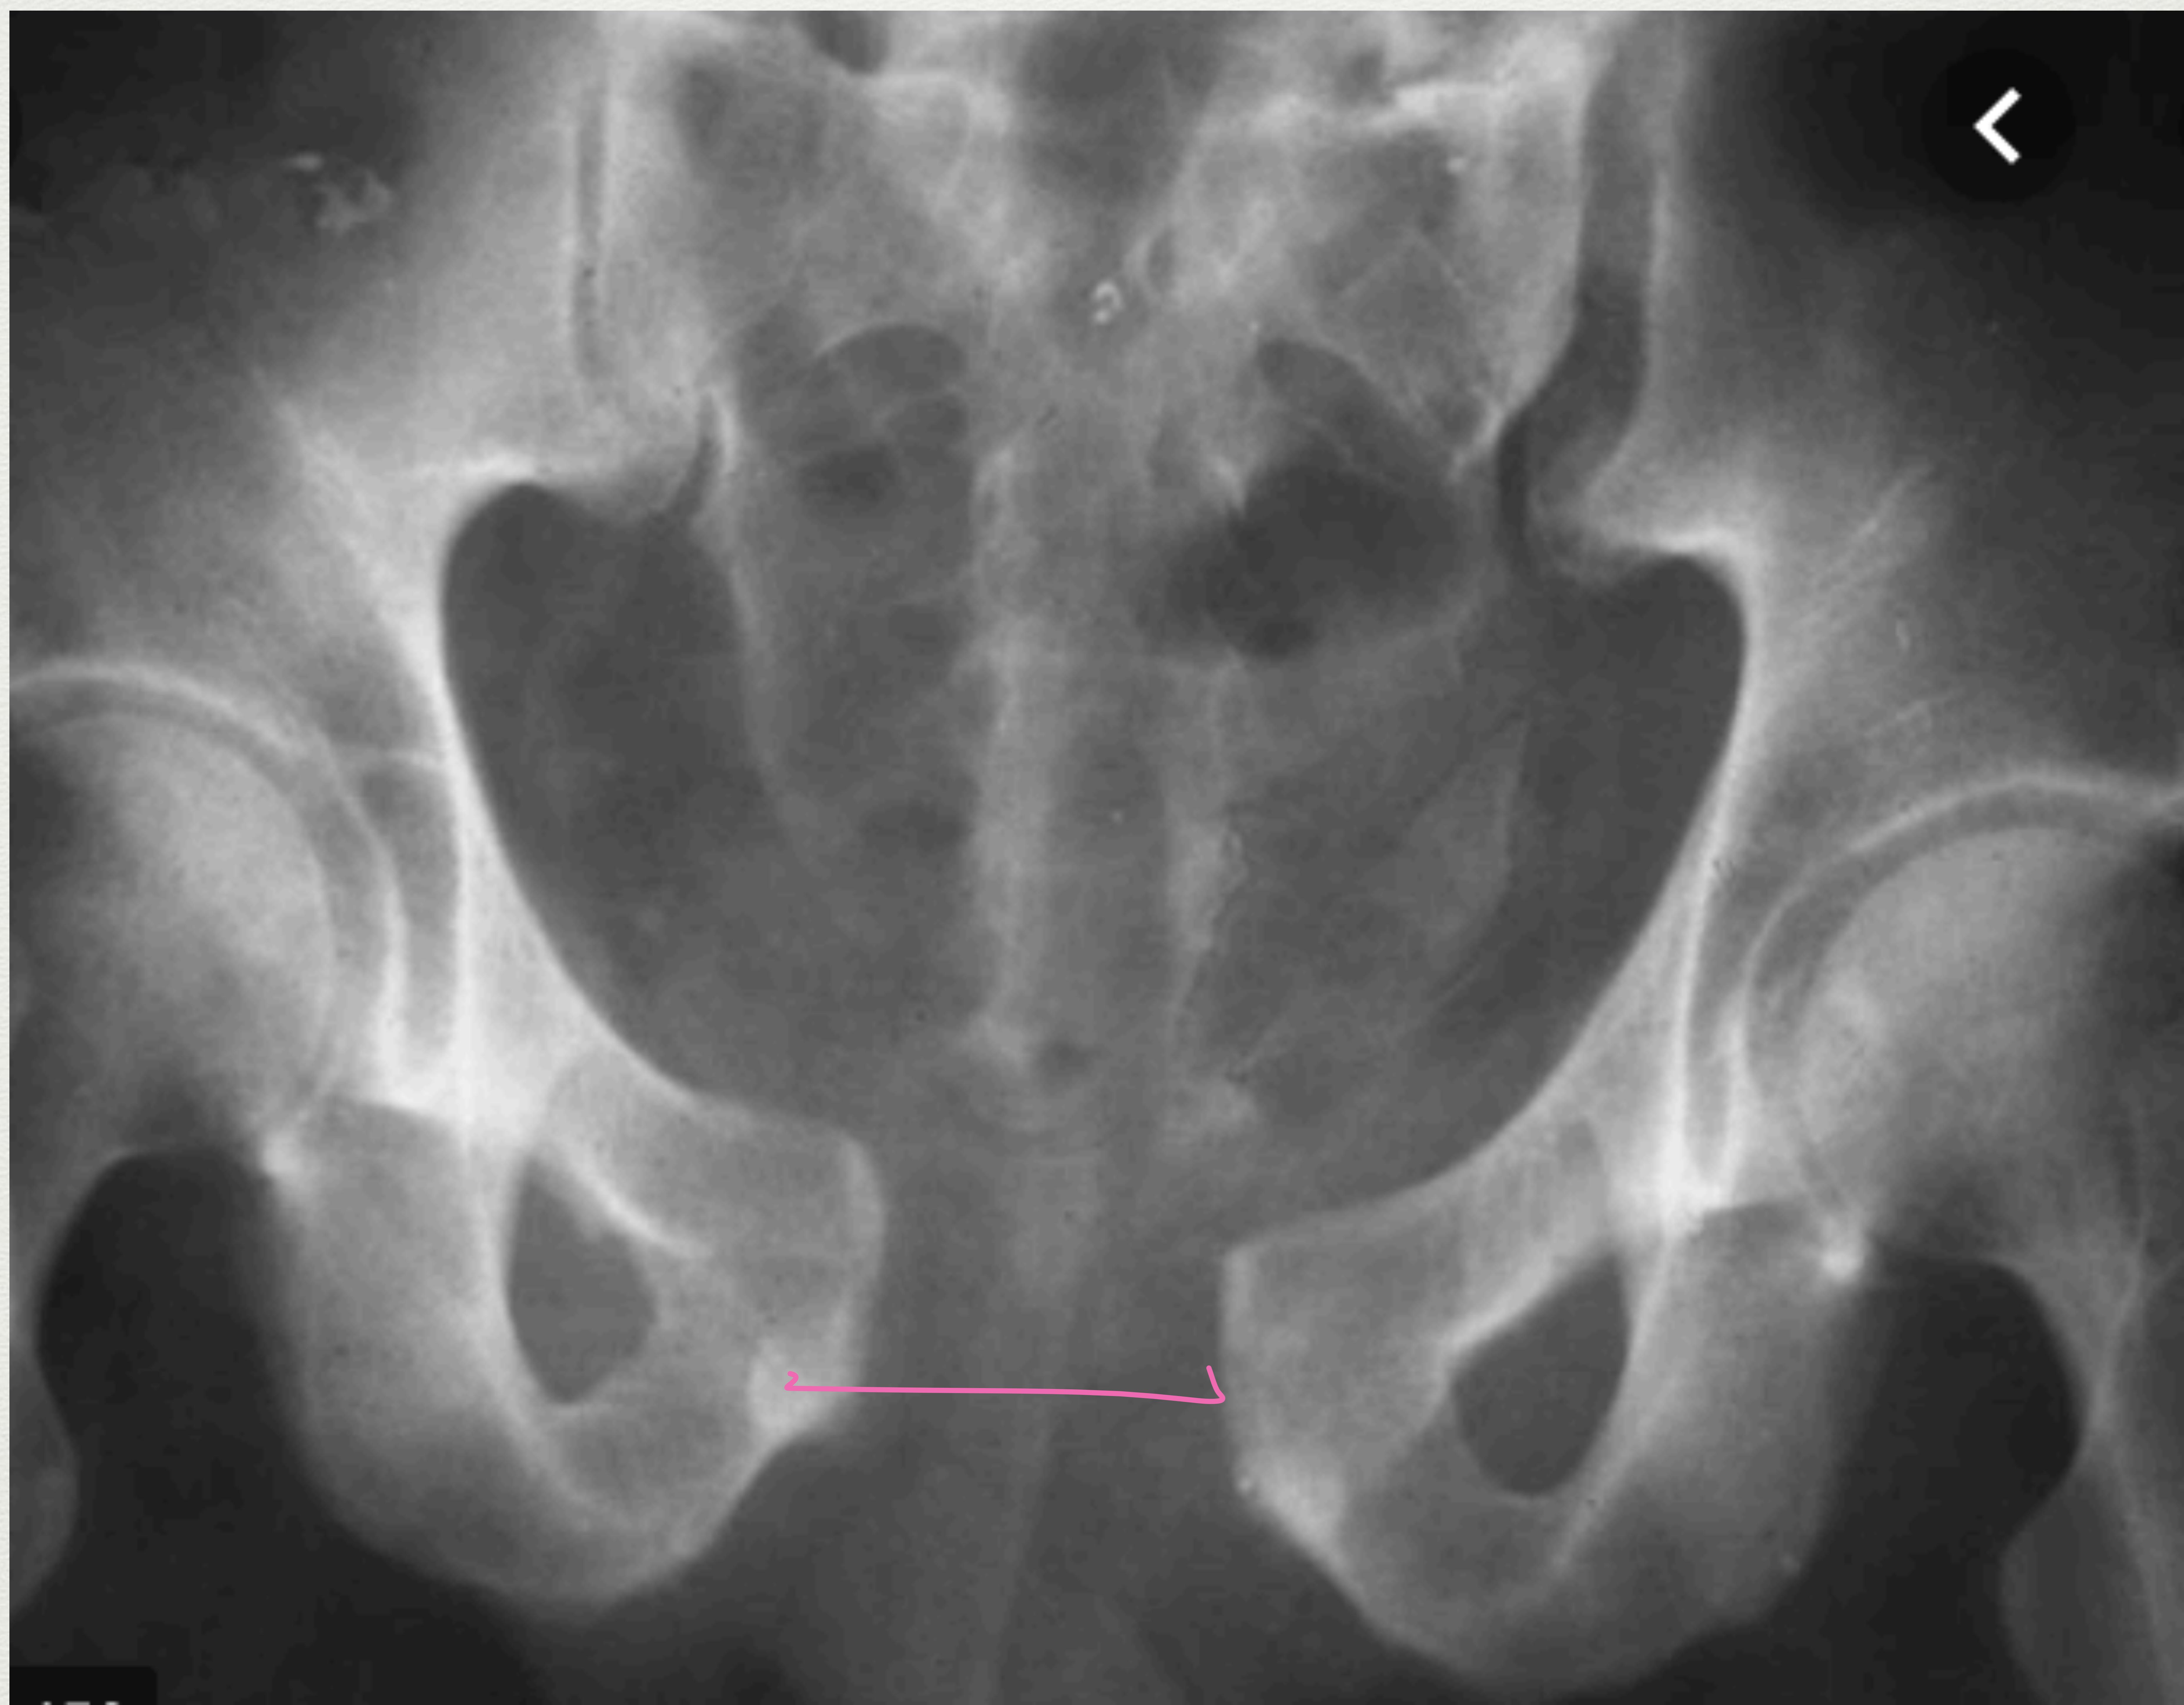

Classification: Open Book Fracture

Pelvic X-ray showing a large separation (diastasis) between the pubic bones, characteristic of an open book pelvic fracture (>3cm).